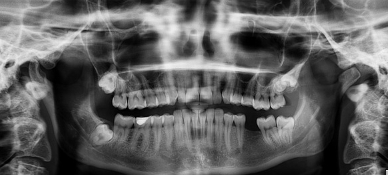

치아의 구조

치아는 크게 세 부분으로 나뉩니다:

- 치관(齒冠):

입 안에서 보이는 부분으로, 음식물을 직접 부수고 씹는 역할을 합니다.- 법랑질: 치아 표면을 덮고 있는 가장 단단한 조직.

- 상아질: 법랑질 아래에 위치하며, 치아의 주된 구조를 이룹니다.

- 치경(齒頸):

잇몸과 접촉하는 부분으로, 치아와 잇몸을 연결하는 역할을 합니다. - 치근(齒根):

잇몸 안쪽에 박혀 있는 부분으로, 치아를 턱뼈에 고정시키며 안정성을 제공합니다.- 치근은 치수(신경과 혈관이 모여 있는 부분)를 보호합니다.

치아의 종류

사람의 치아는 역할에 따라 여러 종류로 나뉩니다:

- 앞니(절치)

- 위치: 입의 앞쪽

- 기능: 음식을 자르고 깨무는 역할

- 송곳니(견치)

- 위치: 앞니 옆

- 기능: 음식물을 찢고 강하게 물어뜯는 역할

- 어금니(구치)

- 위치: 입의 뒤쪽

- 기능: 음식을 갈고 부수는 역할

- 소구치와 대구치로 나뉩니다.

- 사랑니(제3대구치)

- 위치: 어금니의 가장 뒤쪽

- 기능: 현재는 기능이 거의 없으며, 일부 사람에게는 아예 나지 않기도 합니다.